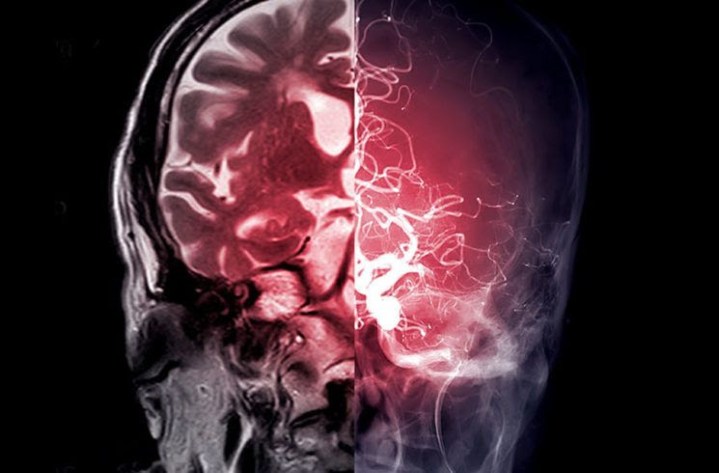

Un primer ensayo en humanos de estimulación cerebral profunda (ECP) para pacientes en rehabilitación tras un accidente cerebrovascular realizado por investigadores de Cleveland Clinic demostró que el uso de ECP dirigida al núcleo dentado – que regula el control fino de los movimientos voluntarios, la cognición, el lenguaje y las funciones sensoriales del cerebro – es seguro y factible.

Cada participante se sometió a una intervención de ECP, que consistió en la implantación quirúrgica de electrodos en una parte del cerebro llamada cerebelo. Una vez conectados a un dispositivo similar a un marcapasos, los electrodos se utilizaron para administrar pequeños impulsos eléctricos que ayudarán a las personas a recuperar el control de sus movimientos.